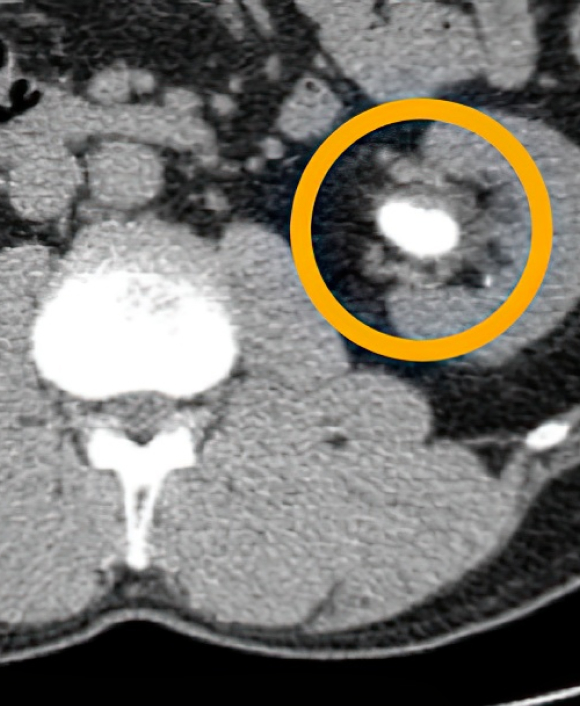

요로결석 환자의

복부CT 영상

유로닷 AI는 보건복지부가 혁신의료기술로 지정한 CT 기반 인공지능 결석 검출 솔루션입니다.